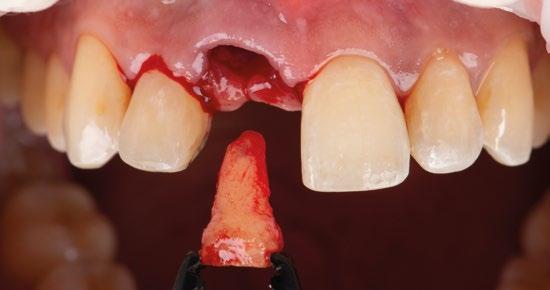

1.- Quitamos la corona ferulizada. (Figura 15)

2.- Extraemos de manera meticulosa la raíz del diente afectado. (Figura 16)

3.- Legramos toda la zona del lecho implantario con el fin de poder eliminar cualquier resto de tejido de granulación.

4.- Desepitelizamos en margen gingival. (Figura 17)

5.- Tunelizamos el defecto vestibular para alojar el injerto de tejido conectivo. (Figura 18)

6.- Colocamos injerto de tejido conectivo. (Figura 19)

7.- Interponemos membrana reabsorbible entre tejido conectivo y alveolo. (Figuras 20 y 21)

8.- Realizamos osteotomía mediante férula quirúrgica utilizando fresa piloto. (Figuras 22 a 24)

9.- Seguimos preparando el lecho utilizando fresado biológico con la OsseoShaperTM. (Figura 25)

10.- Colocamos implante Nobel Biocare N1TM TiUltra de 3,5x13. (Figura 26)